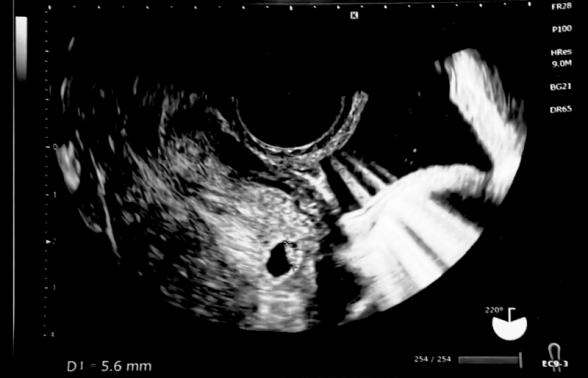

本日7wジャストで胎嚢10ミリ、胎芽5.6ミリ、心拍確認できました。

ただ、1日1ミリ程度成長すると聞いていたので、2週間で胎嚢が5ミリちょっとしか成長していません。